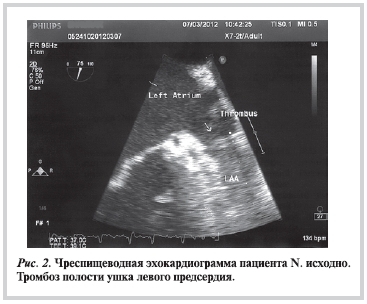

Было принято решение о проведении ЧП-ЭхоКГ для определения возможности и целесообразности восстановления синусового ритма. На 2-й день лечения была выполнена ЧП-допплер-ЭхоКГ: в УЛП визуализировался рыхлый тромб с частично подвижной головкой, выявлено значительно выраженное спонтанное контрастирование в полости ЛП (рис. 2), в связи с чем синусовый ритм не был восстановлен.

За время стационарного лечения стабилизировалось артериальное давление, улучшилась переносимость нагрузки, но сохранялись одышка, слабость, чувство неритмичного сердцебиения. Больной был выписан с рекомендациями о дальнейшем приеме дабигатрана 110 мг 2 раза в день и повторном выполнении ЧП-допплер-ЭхоКГ через 4 нед для растворения внутрисердечного тромба.